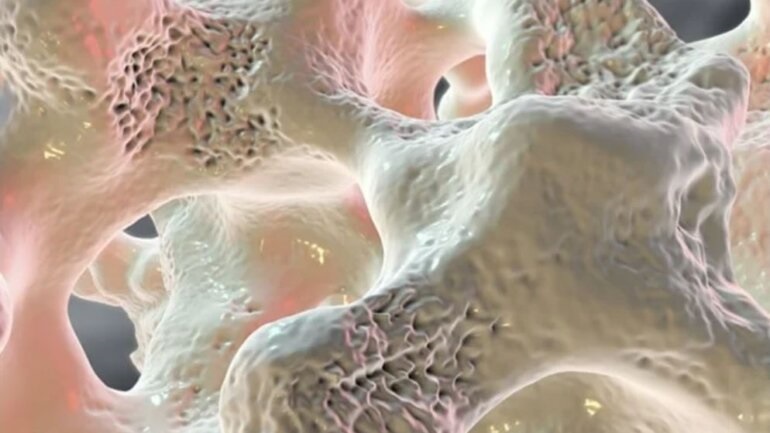

Ο περιορισμός βάδισης αυξάνει τον κίνδυνο κατάγματος

Ο περιορισμός στο περπάτημα σχετίζεται σημαντικά με τον κίνδυνο κατάγματος σε μια διάρκεια 4-5 ετών, σύμφωνα με μια μελέτη που δημοσιεύθηκε στο JAMA Network Open.